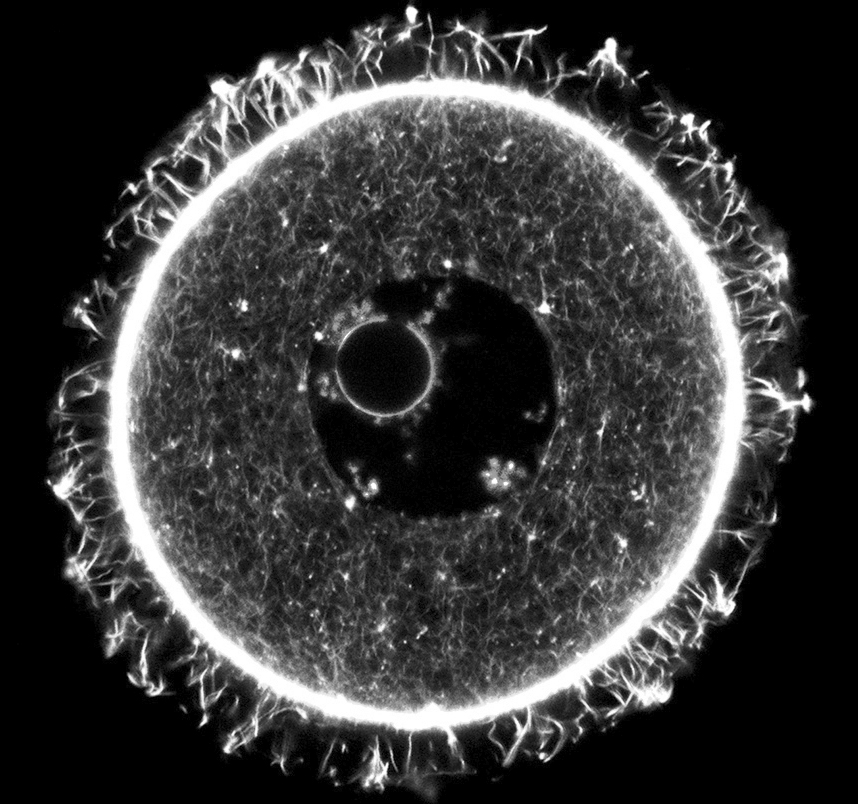

मैक्स प्लांक इंस्टीट्यूट फॉर मल्टीडिसिप्लिनरी साइन्सेज़ की मेलिना शू के नेतृत्व में काम कर रहे समूह ने 8 सप्ताह आयु के चूहों के अंडाणुओं का विश्लेषण किया। गौरतलब है कि 8 सप्ताह की आयु चूहों के हिसाब से प्रजनन का शिखर होता है। विश्लेषण से पता चला कि इन अंडाणु कोशिकाओं में तकरीबन 10 प्रतिशत प्रोटीन उस समय बने थे जब ये मादा चूहे अपनी मां के गर्भाशय में थे। ये नतीजे नेचर सेल बायोलॉजी में प्रकाशित हुए हैं।

जब उन्होंने लगभग 15 माह आयु के चूहों के साथ यह प्रयोग दोहराया तो गणितीय मॉडल विश्लेषण से पता चला कि 10 प्रतिशत से अधिक प्रोटीन्स का अर्ध-जीवन काल 100 दिन से अधिक है। अर्ध-जीवन काल यानी उतने समय में उनमें से आधे अणु विघटित हो जाएंगे। ध्यान रहे कि 100 दिन मतलब चूहे की आयु का 13 प्रतिशत होता है।

पेनसिल्वेनिया विश्वविद्यालय की एवा बोम्बा-वार्कज़ैक के नेतृत्व में एक अन्य समूह को भी ऐसे ही नतीजे प्राप्त हुए, जो उन्होंने ईलाइफ नामक पत्रिका में प्रकाशित किए हैं। 7 माह के चूहों के अंडाणुओं में प्रोटीन के विश्लेषण से पता चला कि इनमें से कम से कम 5 प्रतिशत का संश्लेषण जन्म से पहले या तत्काल बाद हुआ था। 11 माह की उम्र तक टिकाऊ प्रोटीन्स में से 10 प्रतिशत शेष थे।

ऐसा लगता है कि ये दीर्घजीवी प्रोटीन अंडाणुओं की हिफाज़त करते हैं और साथ ही यह भी स्पष्ट होता है कि इन प्रोटीन के क्रमिक विघटन के साथ अंडाशय में अंडाणुओं की संख्या घटती जाती है और एक समय के बाद मादा प्रजननक्षम नहीं रह जाती। इसी को रजोनिवृत्ति या मेनोपॉज़ कहते हैं। (स्रोत फीचर्स)